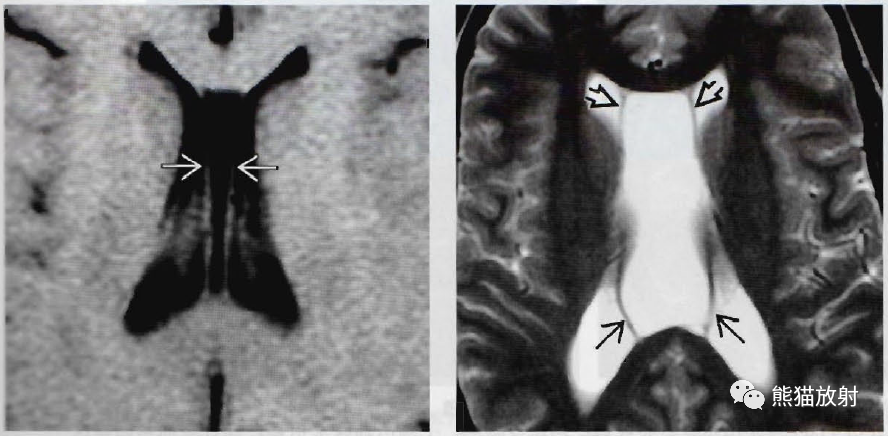

(左) 轴位T1WI显示伴有韦尔加腔的小透明隔腔。注意位于侧脑室前角及体部之间的指状脑脊液积聚。

(右) 轴位T2WI显示伴韦尔加腔的透明隔腔变异。注意透明隔两分叶间的巨大脑脊液积聚图向后直接延续,将穹隆向侧方张开。